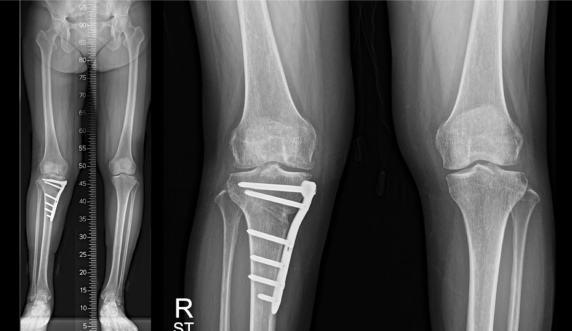

수술 후 1년